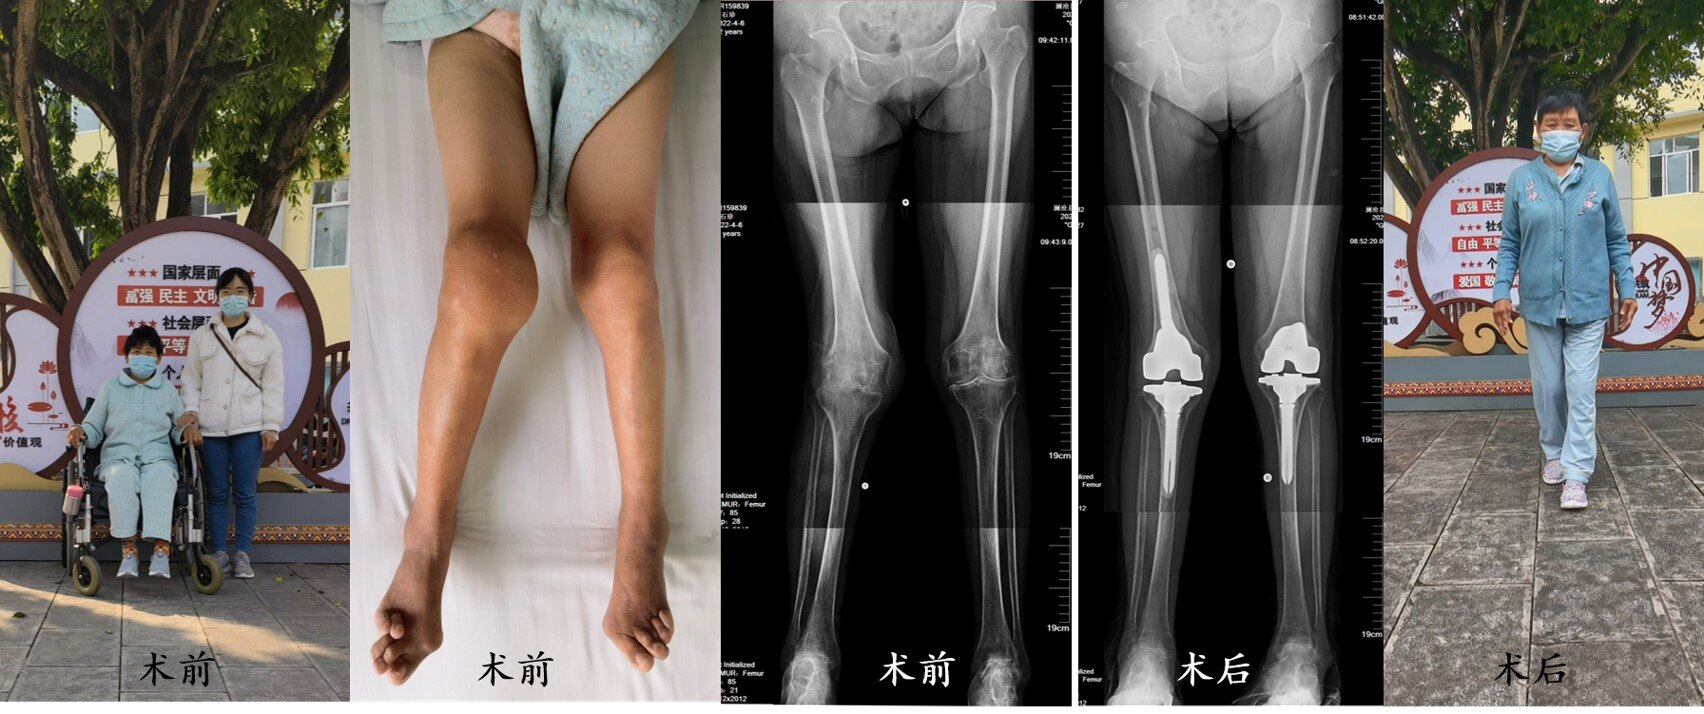

病例1(图4): 55岁的李女士患有类风湿性关节炎30余年,双侧膝关节疼痛、肿胀、变形、屈伸活动严重受限,平日生活中难以下床行走,需要坐轮椅出行,常年的关节病痛严重影响了李女士的生活质量。在澜沧县第一人民医院骨科的帮助下,先后成功完成了双侧人工膝关节置换手术,经过康复锻炼,术后6周时李女士已经可以自主行走活动。

图4. 李女士因双膝类风湿性关节炎接受了双侧人工膝关节置换手术。

病例2(图5):50岁的周先生患有类风湿性关节炎20余年,由于一直没有进行正规的药物治疗,以致于双手、双膝关节、双踝关节等全身多个关节遭受严重的侵蚀破坏。来到澜沧县第一人民医院骨科就诊时,周先生已经不能自主站立,需要依靠双拐支撑勉强站立行走,多年来借助轮椅出行。于是,周先生接受了双侧人工膝关节置换手术,手术以后身体健康逐步恢复,在术后6周时已经开始脱离拐杖行走锻炼。

图5. 周先生因双膝类风湿性关节炎接受了双侧人工膝关节置换手术。